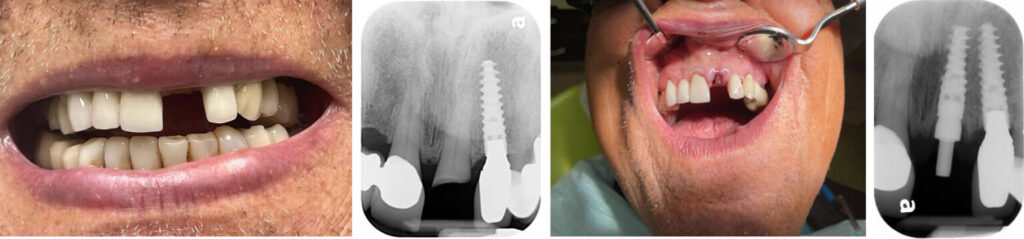

Broken Front Tooth Emergency Treatment

Implant and Temporary Crown within One Hour

Emergency exams booked within 2 hours. Emergency Implant treatment scheduled within 24-48 hours from exam. We offer a FREE Consultation and FREE Low Radiation X-Rays. A broken or knocked-out front tooth is more than a dental problem. It’s an immediate aesthetic and functional emergency. Our clinic provides urgent assessment and dental implant treatment to replace a damaged front tooth with a secure, natural-looking solution. Using premium Nobel Biocare implant systems, we restore your smile with precision shade-matching and gum line aesthetics so your new tooth blends seamlessly with the rest of your smile.

In many cases, we can place the implant promptly after evaluation and provide a temporary tooth the same day, so you never have to leave with a visible gap. Dental implants also preserve the jawbone and prevent neighbouring teeth from shifting and making them the most stable, long-term replacement for a broken front tooth.

Over 25 years’ experience successfully performing dental implants. We can remove your broken tooth and insert the implants – all in the same day! Interest-free Financing Options are available.